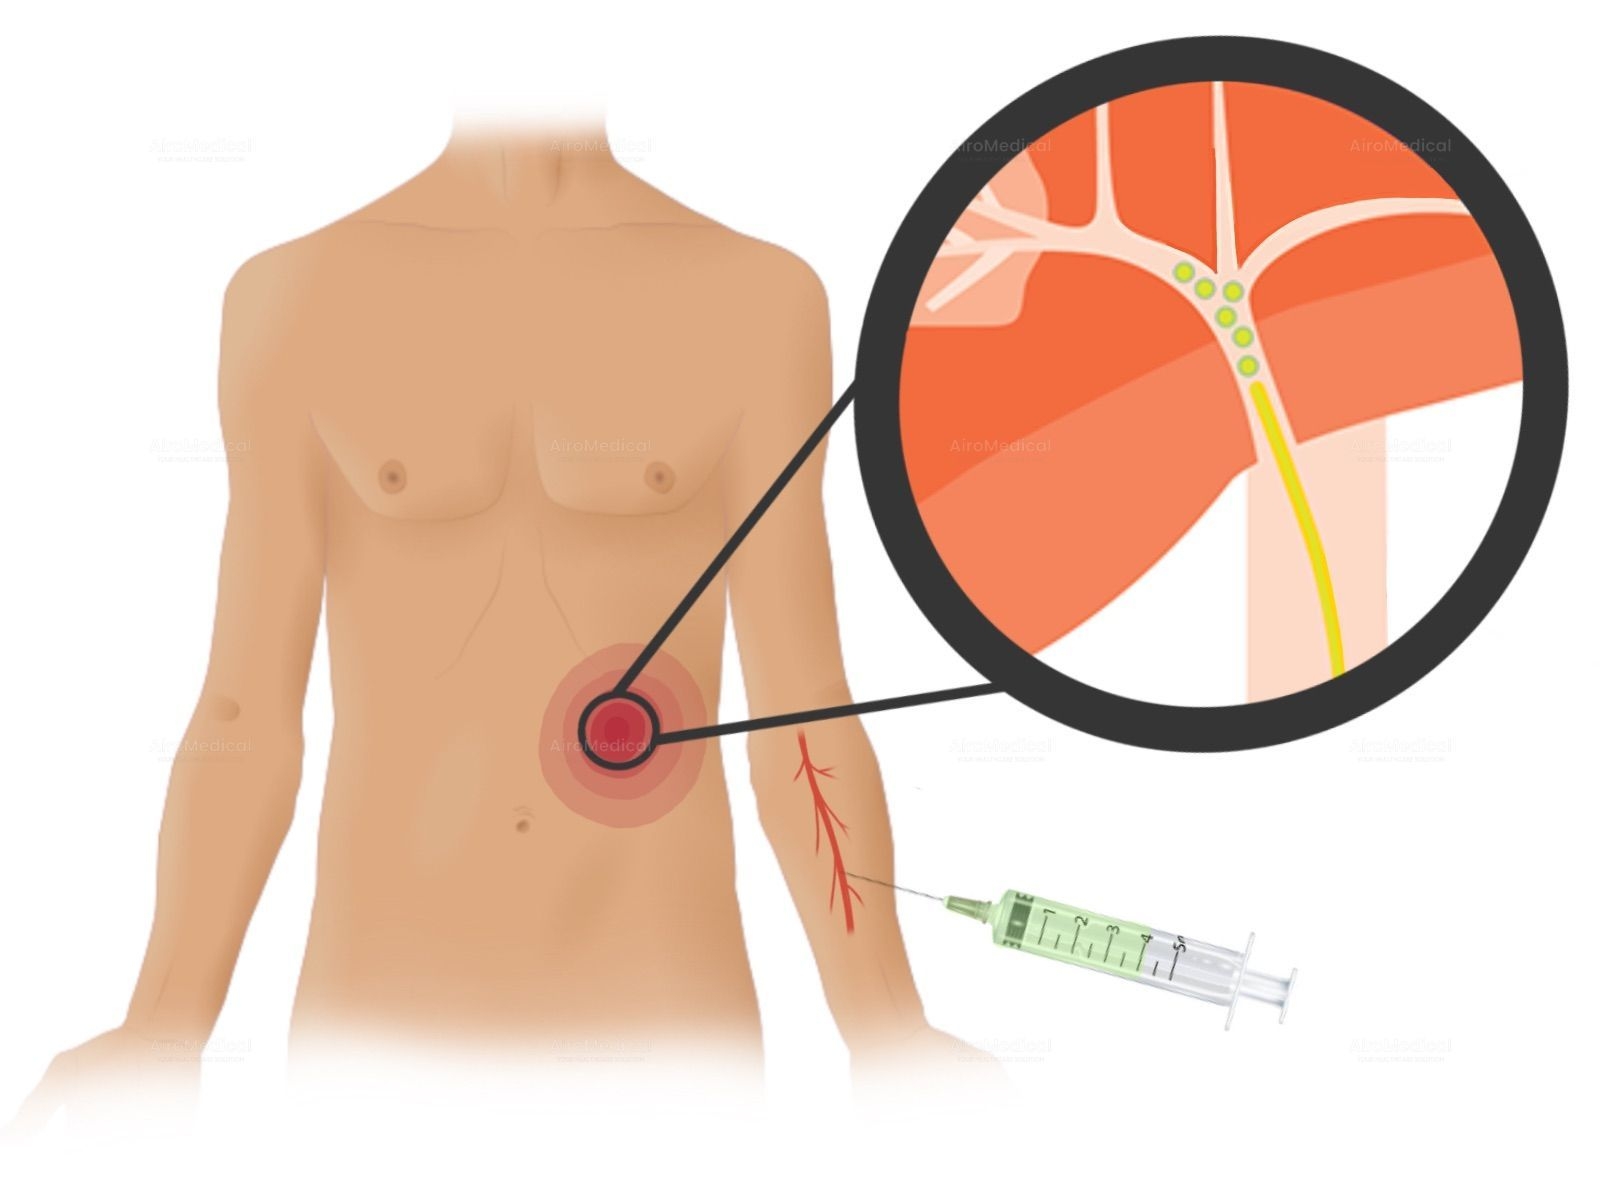

What modern technical equipment does the hospital include?

Among the leading technical equipment: are a gamma scalpel and a DaVinci robot. GammaKnife is an ultra-modern radiosurgical device that successfully treats tumors without open surgery. At the same time, DaVinci is designed to perform complex operations minimally-invasively.

Is University Hospital Frankfurt suitable for patients with cancer?

It is one of the largest institutions dealing with cancer treatment. The oncology unit has a spiral tomograph, a gamma knife, PET, and other latest-generation equipment. Moreover, the team has performed hundreds of successful operations to treat the most complex oncological diseases.